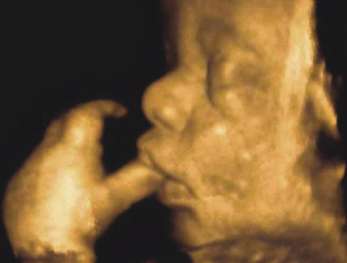

Dr. Sawant Diagnostic & Sonographic Centre - Image 1 Dr. Sawant Diagnostic & Sonographic Centre - Image 2 Dr. Sawant Diagnostic & Sonographic Centre - Image 3 Dr. Sawant Diagnostic & Sonographic Centre - Image 4